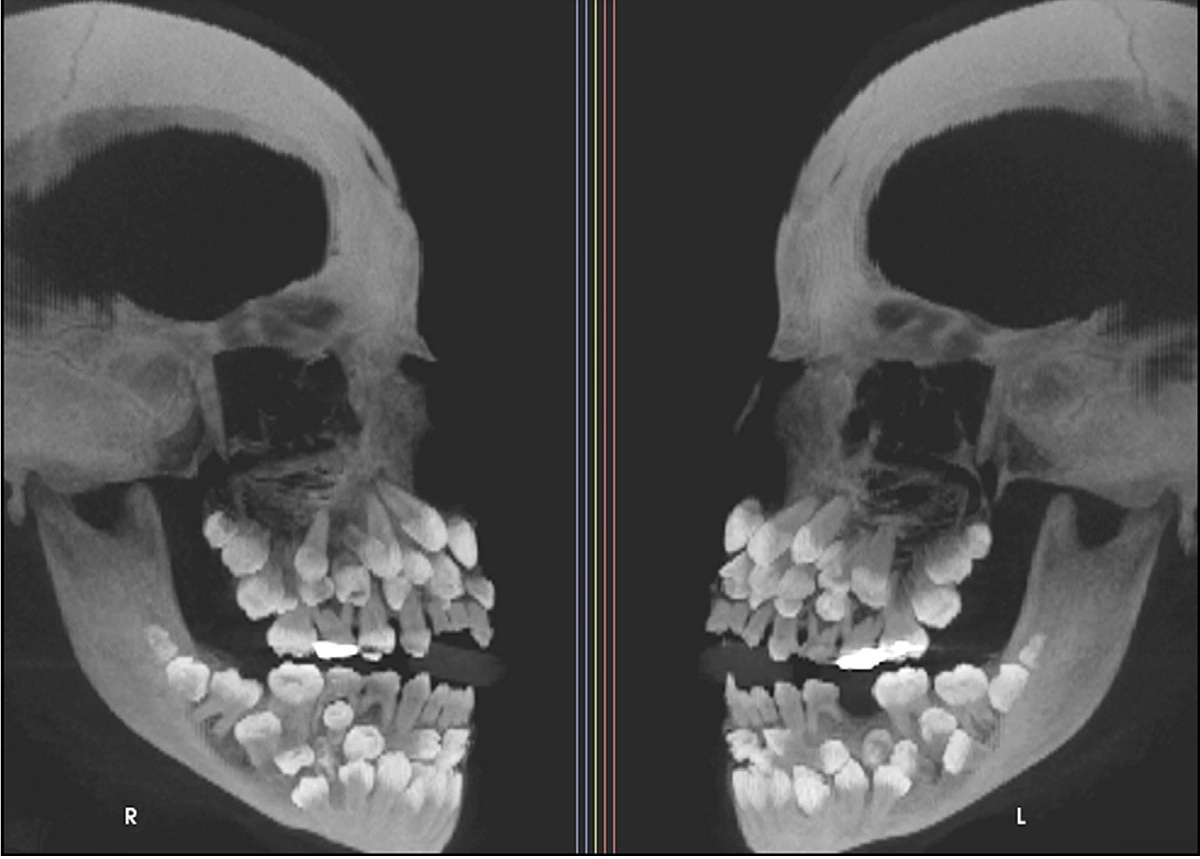

그러나 이어진 엑스레이 촬영 결과는 의료진을 충격에 빠뜨렸다. A양 입안에서 유치 18개와 영구치 32개, 과잉치 31개 등 총 81개 치아가 발견된 것.

이는 '다발성 과치증'(multiple hyperdontia)이라는 질환으로 성인 기준 정상 치아 개수인 32개를 넘어 더 많은 치아를 갖는 선천성 발달 이상이다.

다만 과잉치는 1~2개 정도만 발견되는 게 일반적이다. 이번처럼 30개 넘는 과잉치가 확인된 사례는 전 세계적으로도 매우 드물다.

일부 과잉치는 잇몸 속에 깊이 묻혀 있거나 정상 치아와 형태가 유사해 정확한 구분이 쉽지 않다. 무작정 발치할 경우 턱뼈 손상 우려도 있다.